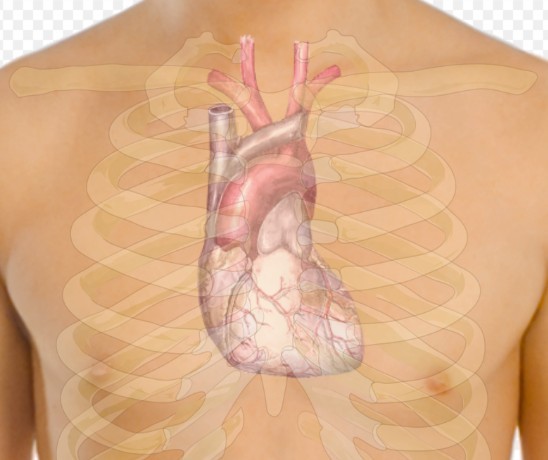

Первым указанным признаком является учащенное сердцебиение, особенно если оно наблюдается без физической активности. Также отмечается, что повышенный пульс после тренировок может свидетельствовать о проблемах с сердцем.

Следующий признак, выделяемый врачом — низкий пульс, который для спортсменов может быть нормой. Боль в груди может указывать на ишемическую болезнь сердца, а нарушения дыхания также требуют внимания кардиолога.

Отечность ног может быть еще одним признаком проблем с сердцем, хотя она также может свидетельствовать о венозных проблемах. Врач подчеркивает, что обнаружение хотя бы одного из этих признаков является серьезным поводом для консультации с врачом, чтобы предотвратить возможные ухудшения здоровья, сообщает В Татарстане.